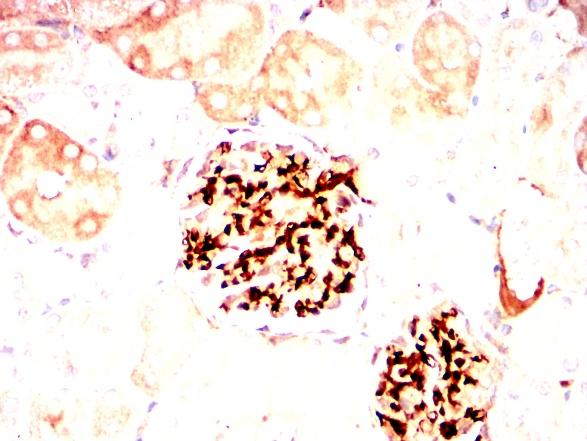

利用THY1小鼠单抗结合DAB染色对石蜡包埋大鼠肾脏的免疫组化分析。 |